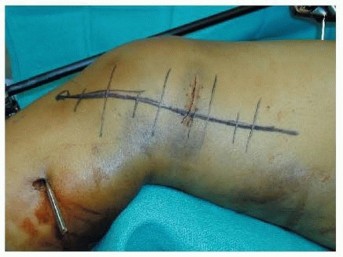

### FIG 3 • A. Patient with a grade IIIA open distal femur with extruded fragment; the “extension” of the femoral condyles is outlined. B. Patient with a distal femur fracture with intercondylar extension showing the subtle rotational deformities of the individual condyles. C. The muscle forces are shown on the distal femur, as is the femoral artery and vein entering the canal of Hunter (arrow). The adductor magnus inserts on the adductor tubercle, leading to a varus deformity of the distal segment. D. A lateral image of the same patient with the popliteal artery and tibial nerve drawn in to show the relative proximity to the fracture ends. 468

### FIG 5 • A-C. Patient with a spiral distal-third femur fracture that appears to be extra-articular. A. In the AP radiograph, the knee is not fully visualized. B. A dedicated knee AP radiograph shows the spiral distal-third femur fracture. Note the intra-articular injury and the gap at the fracture (arrows). C. Lateral view of the knee. Again note the coronal fracture of the medial femoral condyle (type B3). D-F. Plain radiographs of a patient with a grade II open distal femur fracture. G,H. Patient with a dosed femur fracture that was initially thought to be extra-articular. 470